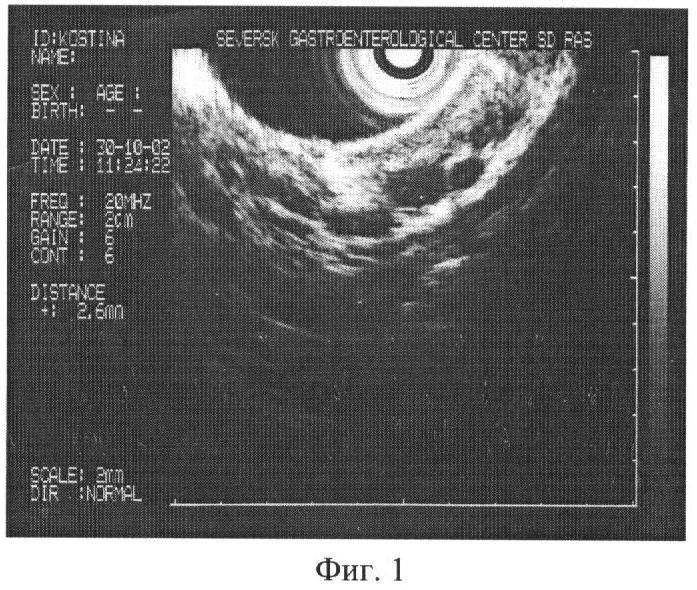

Через 2 года кровотечение рецидивировало. Больная поступила в клинику. При обследовании определено расширение вен пищевода I степени – до 2,6 мм в диаметре (фиг.1).

Проведено исследование согласно предлагаемому способу. В желудке выявлены варикозные изменения венозных сосудов. Верифицирована одна из вен, явившаяся источником рецидивного кровотечения, – 4 мм в диаметре (фиг.2). Таким образом, расширение вен желудка диаметром 4 мм свидетельствует о наличии риска кровотечения.